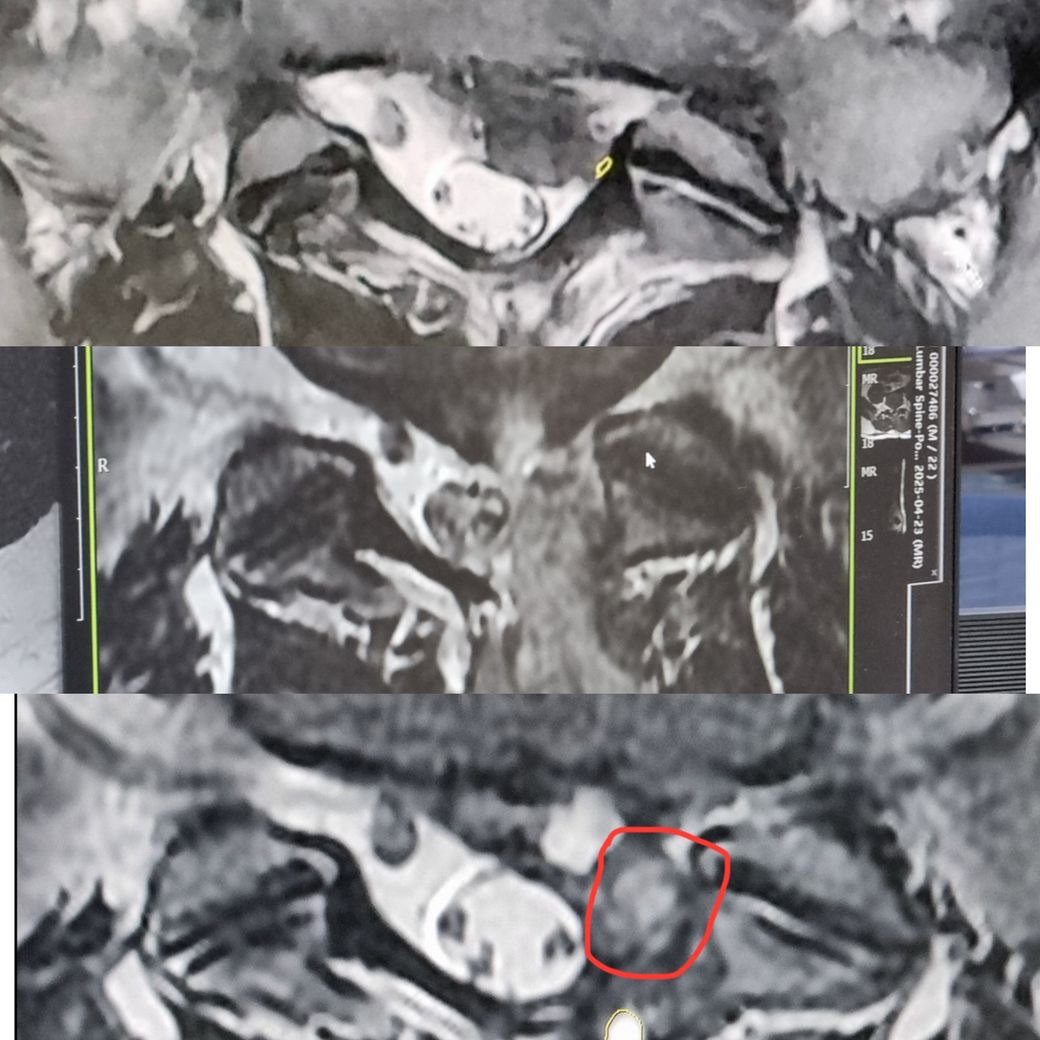

안녕하세요 허리디스크 5-1탈출로 인해 4/22에 양방향 내시경 수술을 했습니다.

수술 후에도 지속되는 엉덩이,꼬리뼈,엉치 통증으로 수술 27일 후에 mri를 다시 찍었습니다.

주치의는 재발은 아니고 현재 신경이 부은 상태고 피고임이 신경을 조금 누르곤 있지만 이는 자연스럽게 흡수되고 호전될 거라고 했습니다.

저는 근데 수술27일 후 단면 사진이 뭔가 재발한 느낌이여서 다른 의사한테 판독을 했지만 그 의사는 재발한거라고 합니다.

차례대로 수술 전/수술 다음날/수술 27일후/수술 27일 후 시상면 입니다.

• 1번 째 사진

• 2번 째 사진

판단이 쉽지 않은 상황이네요.

수술전, 수술 다음날 시상면까지 같이 다시 올려주시면 확인하고 설명드리겠습니다.

그리고 가능하면 수술 27일째의 단면을 올려주신 컷 위아래 2-3개까지 함께 올려주시면 판단에 도움이 되겠습니다.